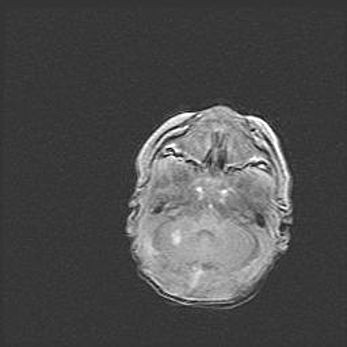

Мальформация Денди-Уокера. Киста задней черепной ямки.

Агенезия мозолистого тела.

Возраст: 2,5 месяца

Вес: 2420 г

Пол: женский

Окружность головы: 37 см

Срок гестации: 32 недели

Мальформация Денди—Уокера — редкий вид патологии ЦНС, представляющий собой врожденный порок развития каудального отдела ствола и червя мозжечка, ведущий к неполному раскрытию срединной (Мажанди) и латеральных (Лушка) апертур IV желудочка мозга. Для этогно синдрома характерна триада симптомов: гипотрофия червя мозжечка и/или полушарий мозжечка, кисты задней черепной ямки, гидроцефалия различной степени. В 70% случаев порок сочетается и с другими аномалиями головного мозга, в частности с агенезией мозолистого тела.